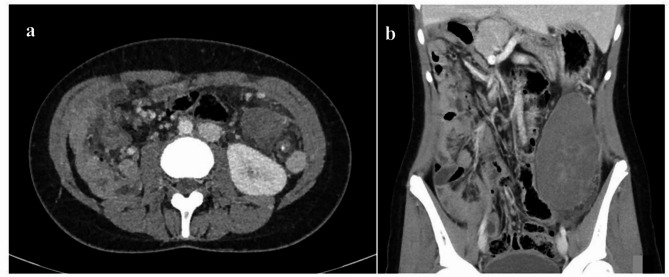

Case presentation: We report on a 14-year-old girl who presented with a 3-day history of left lower abdominal pain and vomiting, with a known history of congenital heart disease associated with Situs Viscerum Inversus and polysplenia. She was found to have normal vital signs but elevated C-reactive protein, and leukocytosis with neutrophilia. In light of the clinical and laboratory data, in addition to the suggestive imaging findings revealed on US and contrast-enhanced abdominal CT, a splenic torsion was suspected. The patient underwent a laparotomy, which confirmed a pedunculated mass in the left flank and iliac fossa, consistent with torsion of one of the spleens, and allowing complete resection of the lesion. The postoperative course was uneventful, and she was discharged after 10 days.